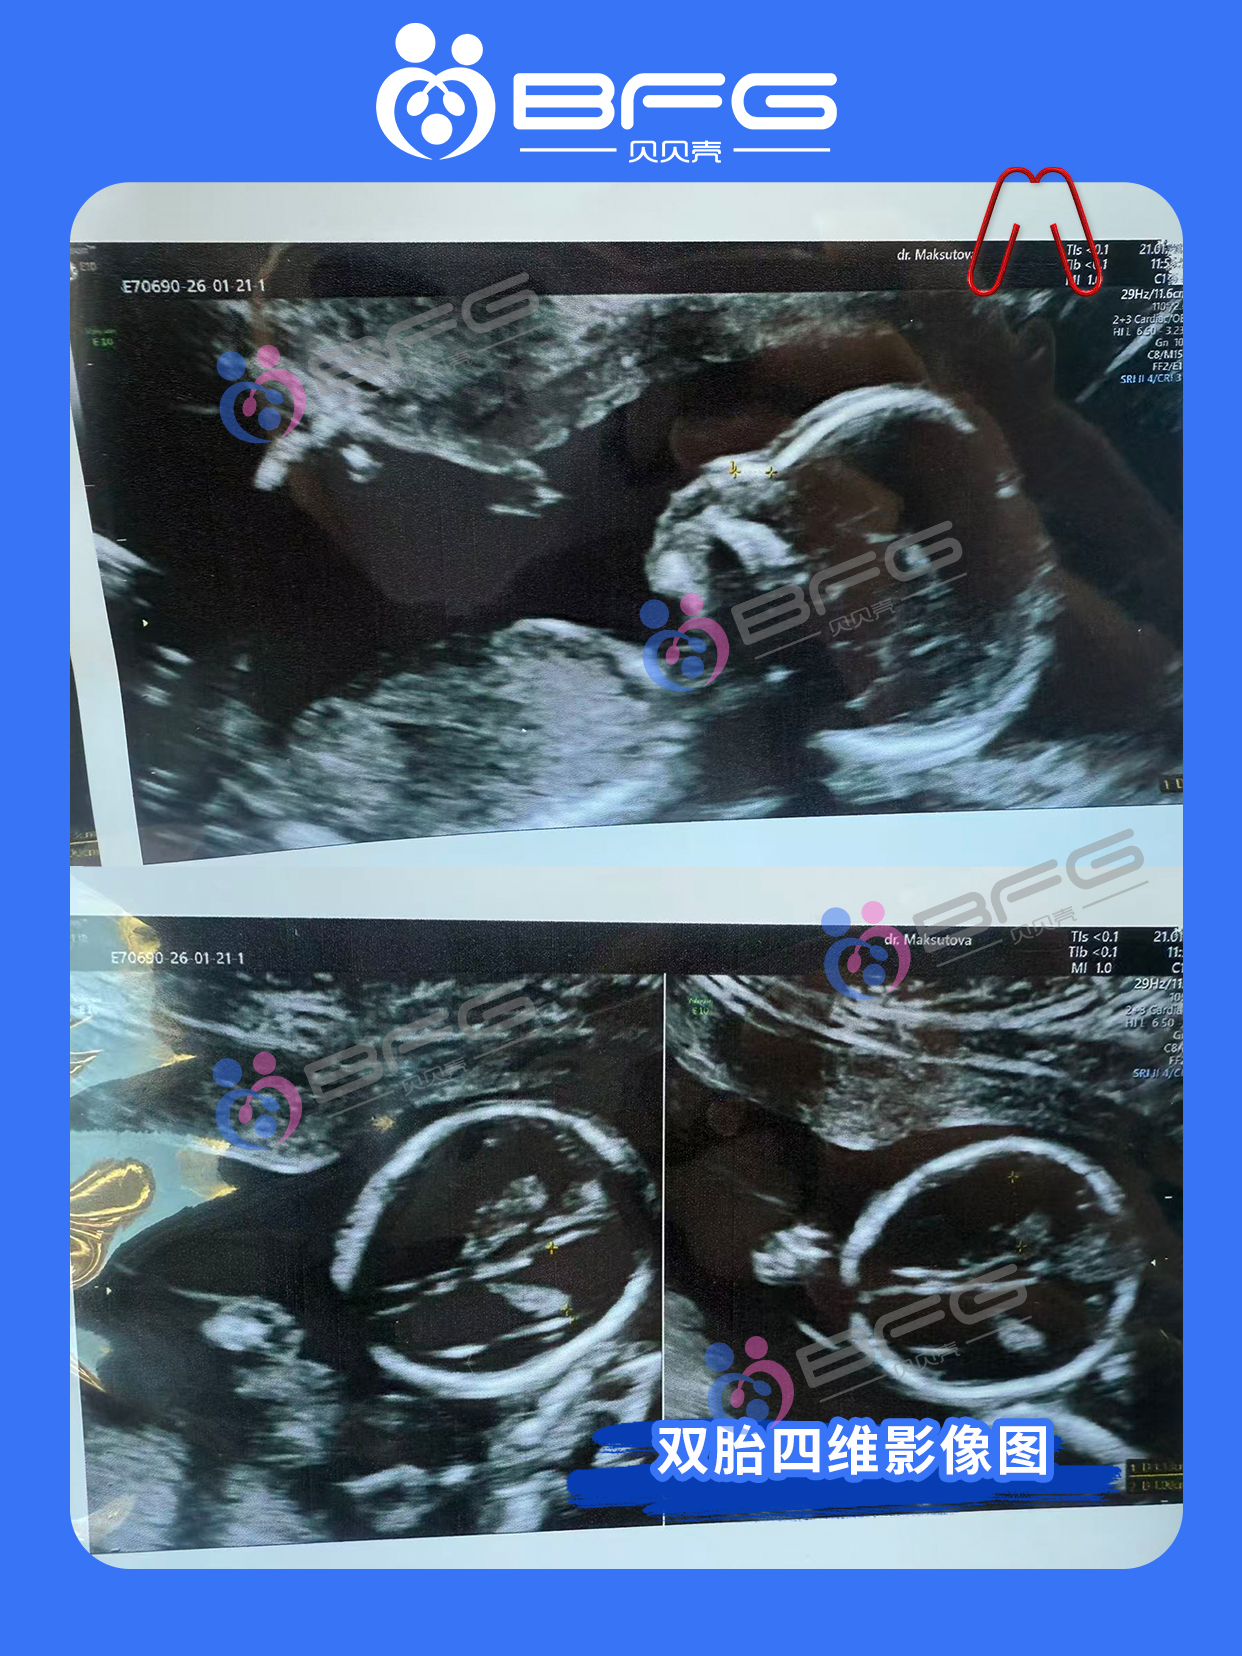

BFG助孕|四维通过,期待与两个宝宝的初见

四维检查顺利通过啦[庆祝],宝宝健康活泼,一切指标都棒棒哒[强]!愿接下来的孕期一路绿灯,平安顺遂,期待与两个宝宝见面的一天~ ❤️